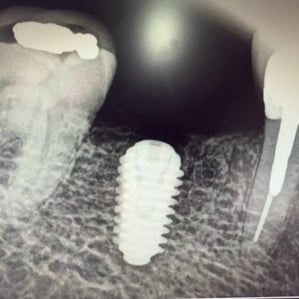

Any idea what implant this is?

There are thousands of implant types — Straumann, MegaGen, Neodent, and more. Each has unique designs, materials, and model numbers. Some are labeled on imaging, many aren’t. Older models, especially, can be hard to trace.

Clues That Help Identification

- Shape and Size: Outline can hint at the manufacturer

- Material Density: Titanium vs. stainless steel shows up differently

- Serial Numbers: Some have tiny etched codes

- Surgical Location: Certain brands dominate specific areas

- Timeframe: Date placed can rule out newer models